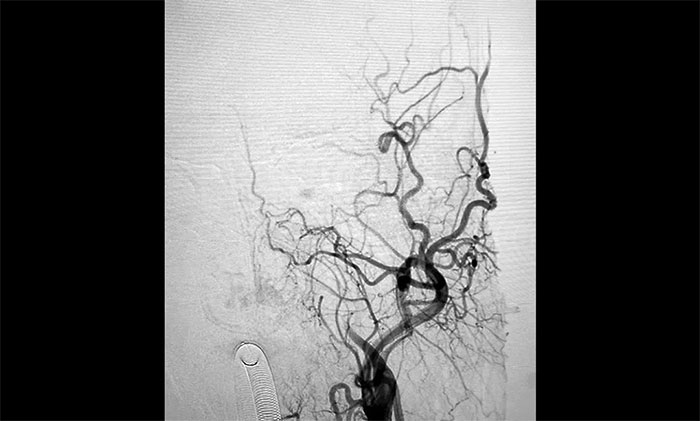

▲术前DSA影像:左侧颈内动脉眼动脉段以远闭塞

术中脑血管造影可见:左侧颈内动脉眼动脉段以远闭塞……余血管未见明显异常。张琪博士在刘春、周林华、李喆医生协助下,通过右侧股动脉穿刺,将微导管、微导丝送达左侧大脑中动脉M1段,经多次抽吸+支架拉栓,顺利取出血栓。造影显示,颈内动脉眼动脉段血流恢复。